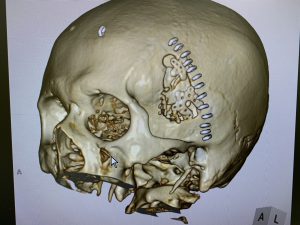

左上の写真は重症の巨大破裂脳動脈瘤(前交通動脈:クモマクシタ出血)で、コイル塞栓できないため右上写真のように開頭による顕微鏡下でのクリッピング術を実施しています。

かなり複雑な形態であったため合計五つのクリップを実施して動脈瘤を完全閉塞させています。